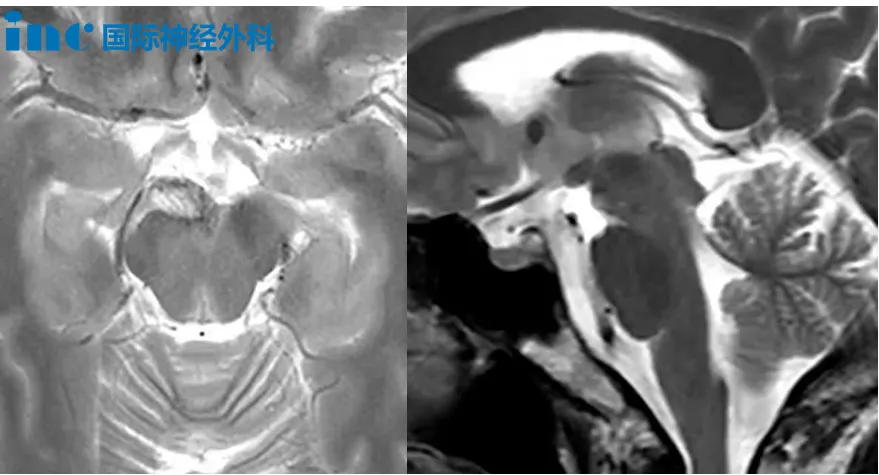

5岁男孩布布,2023年因走路不稳发现颅内占位,于同年9月接受第一次四脑室肿瘤切除手术,术后病理为后颅窝室管膜瘤。2024年5月因肿瘤复发再次接受手术,病理升级为间变性室管膜瘤,WHO 3级。术后布布出现了斜视、眼炎、四肢无力、共济失调、吞咽障碍及言语迟缓等一系列症状。2024年9月完成质子放疗后,近期复查又提示术区边缘出现可疑结节,黏连延髓,疑似再次复发。尽管在治疗过程中,孩子的病情经历了多次挑战,但布布的家人始终没有放弃希望。在得知巴教授来华的消息后,他们希望能为布布争取新的机会。

“幸运的是,肿瘤没有深度侵入脑干内部,而是位于脑干的背侧表面,这意味着这三处病灶在手术上都具有很好的可达性。”当得到巴教授可以手术的评估时,这彷佛绝望中开出的一朵花,让一直揪着心的父母重新看到了希望!